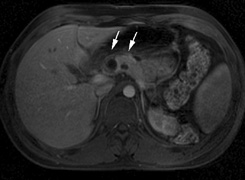

CNS hemangiomas are the most common tumor of VHL, affecting 60% to 80%, with a predilection for the cerebellum and spinal chord. An enlarging cystic component is a frequent finding in symptomatic tumors. Patients typically present in their early 30s; headaches or neck pain in affected individuals should not be ignored.172,173 On microscopy, CNS hemangiomas resemble retinal capillary hemangiomas. Their malignant potential is low.174 The treatment is surgical (Fig. 17, A and B).13

Fig. 17. Images from a 13-year-old boy with Von Hippel-Lindau syndrome. (a) Coronal postcontrast T1-weighted imaging reveals a cystic lesion with an enhancing nodule at the pial surface typical of a hemangioblastoma. (b) A second solid enhancing hemangioblastoma is seen at the craniocervial junction on a sagittal postcontrast T1-weighted image. (c) Associated cystic lesions (arrows) are seen within the pancreas.

PANCREAS.

Pancreatic lesions may be nonsecretory (most commonly cysts or cystadenomas) or secretory (islet cell tumor).179 In one study of 52 patients, 56% (29 patients) were found to have pancreatic lesions. The majority (19 of 29) had cystic changes only (Fig. 17C). Pancreatic lesions were the only abdominal manifestation of disease in 6 of 52 patients.180 In a separate study, pancreatic cysts did not show significant progression on follow-up examinations over an average period of 5 years.181 Like pancreatic cysts, islet cell tumors appear to be frequently asymptomatic.182